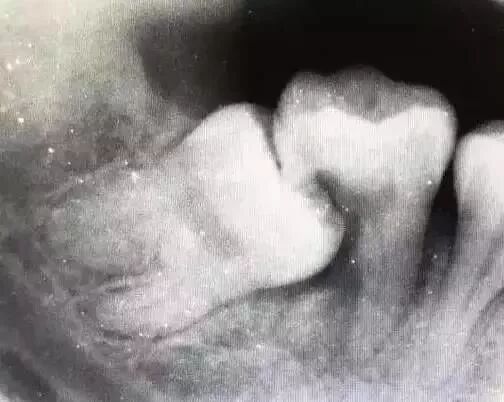

这就是个玉石俱焚的案例智齿把旁边的牙也给顶牺牲了,种牙是在所难免了▼

因为这种智齿水平向前直抵邻牙侧面,形成敞开式间隙,极易存留食物残渣,较难清理,时间一长就可能形成邻面菌斑并产生龋坏,邻牙即进入快速毁灭崩解期。临床上经常出现因为前倾阻生智齿而“拔一送一”的病例。